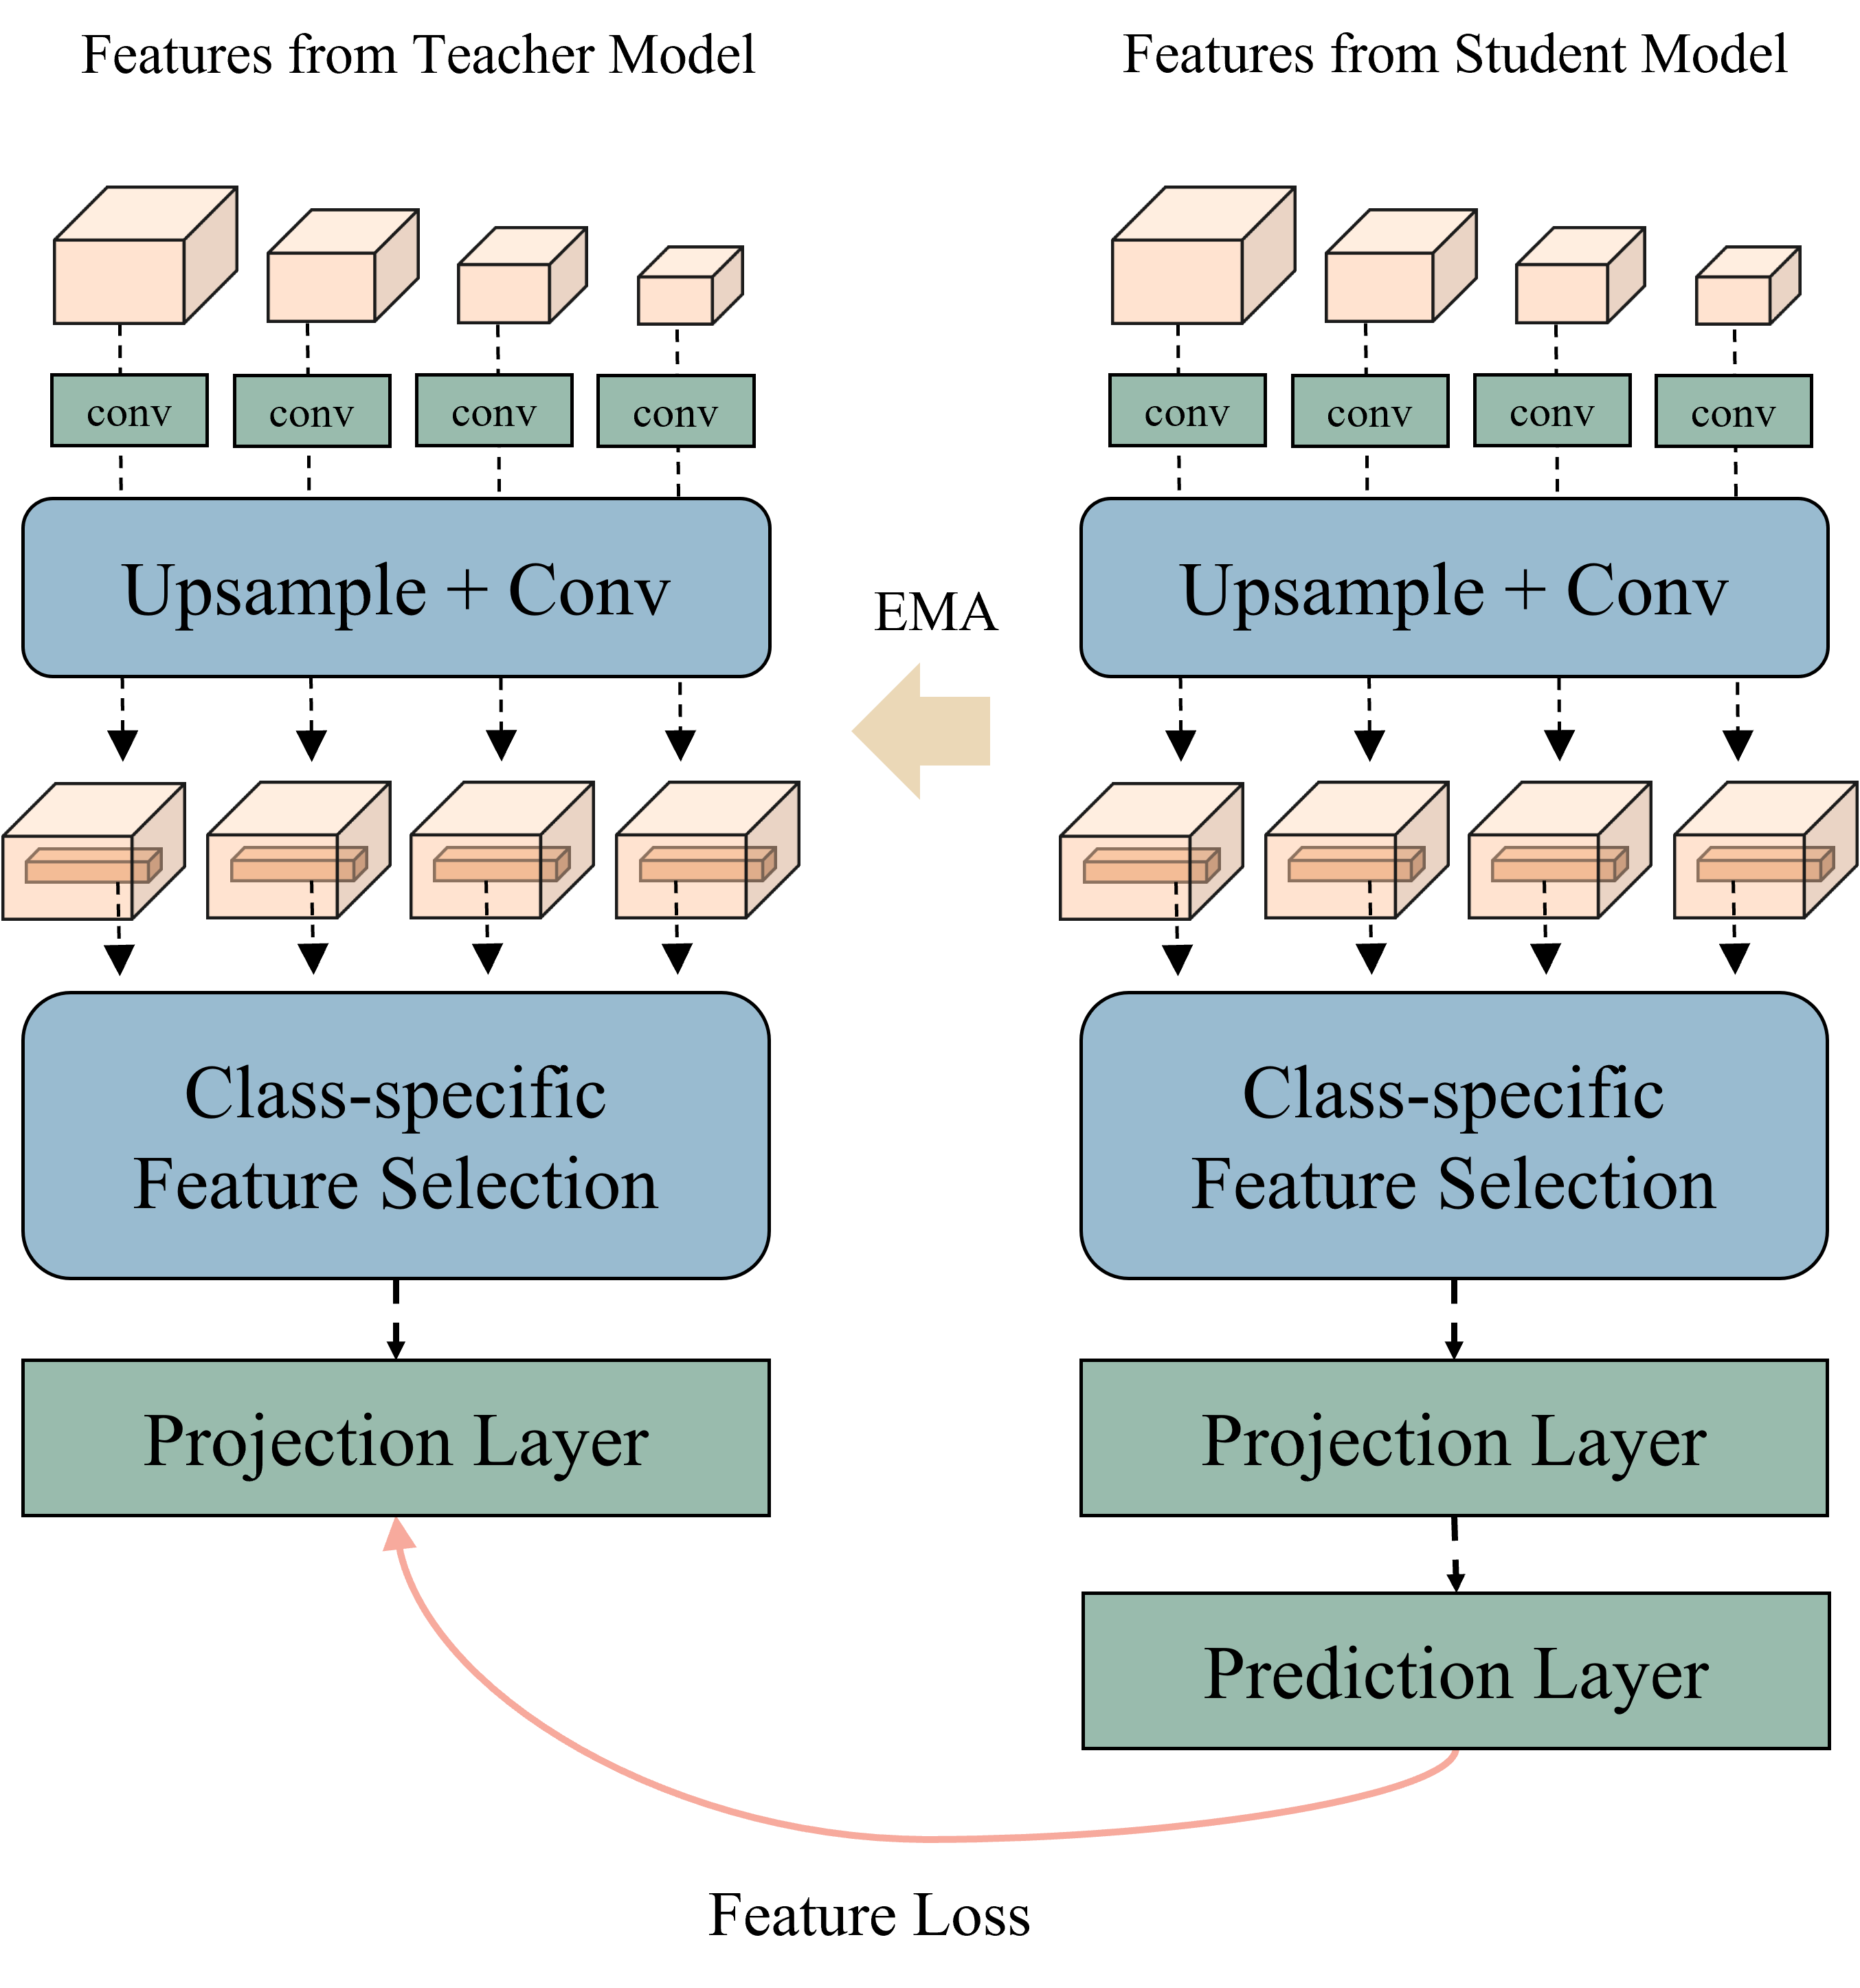

In our previous work [14], we proposed a voxel-level Siamese representation learning method for medical image segmentation tasks. By defining voxel-wise feature relations in the representation space, the model learned feature representations that were effective in the segmentation task. We used the stop-gradient technique and Siamese network from SimSiam [16] to learn voxel-wise feature relations. We also proposed multiresolution feature aggregation method for embedding both local and global features. However, our previous study had two limitations: (1) learning stability and (2) information loss.

In this study, we propose an improved voxel-wise representation learning method for embedding features from labeled data. Inspired by previous studies [15, 31], we used the learning technique from BYOL [15], instead of SimSiam [16], for the first problem(i.e., learning stability). Using EMA from BYOL enabled the model to produce a more stable prediction target [31] than the stop-gradient technique from SimSiam [16]. As presented in Fig. 3b, there are teacher and student models; however, the teacher model uses the slow moving average of the student parameter, instead of learning for its own parameter (i.e., EMA). We update the weights of the teacher as , where represents the decay parameter, and indicates the weights of the student. Furthermore, for the second problem (i.e., information loss), we propose multiresolution context resizing method. The information loss occurs during the downsampling of mask data to match the class location for each voxel-wise feature. Thus, instead of downsampling the mask data, we upsampled the multiresolution features from the encoder, . Figure 3b illustrates the upsampling and convolution stage that can reduce information loss.

As explained in Section III-A, our voxel-wise feature layer (Fig. 2 and Fig. 3b) uses multiresolution features from the encoder of the backbone as an input. These features pass through the upsampling and convolution stages, and voxel-wise features, , are selected for each class; here, refers to the voxel-wise feature from class (class-specific feature selection). These sampled voxel-wise features pass through the projection and prediction layers. The projection layer from the teacher network outputs , and the projection and prediction layers from the student network output , where denotes the prediction layer. Based on a previous research [15], we used the mean square error between normalized and as the feature loss function. The feature loss function for updating the student network can be defined as follows:

where refers to l2-normalization (i.e., ).